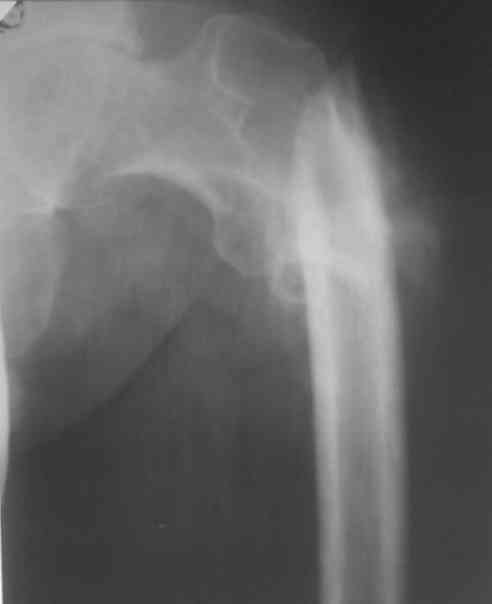

Больной 48 лет, 1,5 года с момента травмы!!Лечился в местной больнице скелетным вытяжением в течение 2 месяцев!!Поступил для оперативного лечения.

Выраженное укорочение конечности на 10 см., с наружной ротацией,С патологической подвижностью.

Уважаемые коллеги - что вы предложите для Коррекции перелома и устранения ложного сустава, и какие виды операций для устранения укорочения!!Какой метод фиксации? С уважением!!!!